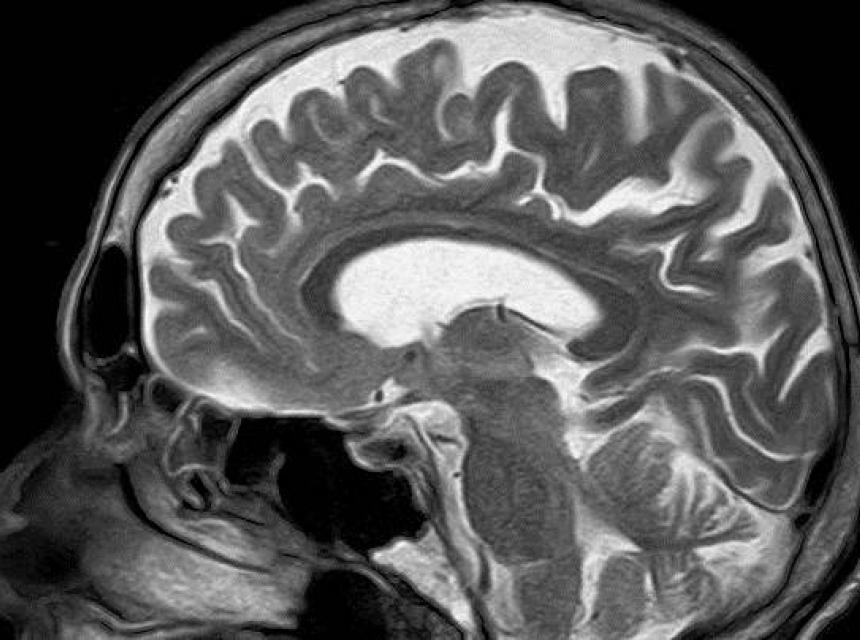

Polovica pacijenata koji su sudjelovali u studiji primili su mjesečnu dozu lijekova, dok je druga polovica ispitanika primila placebo. Kod pripadnika obje su se skupine pokazala poboljšanja kada je riječ o simptomima, a posebice kod onih koji su primili prave lijekove. Nakon 18 mjeseci, kad su svi pacijenti primili dozu proteina, obje su skupine pokazale umjerena do znatna poboljšanja simptoma.. Ipak, skenovi mozga pacijenata koji su primili potrebne proteine pokazali su da se već nakon prve faze liječenja dogodilo znatno poboljšanje, kažu znanstvenici.

"Snimke su pokazale da se lijek, nakon što je stigao u mozak, povezao s ciljem, dopaminskim živčanim završecima, i čini se da pomaže oštećenim stanicama u regeneraciji ili biološkom odgovoru", kaže dr Alan Whone i ističe da postoji mogućnost da bi pacijenti reagirali još i bolje u slučaju veće doze lijekova, prenosi Jutarnji list.